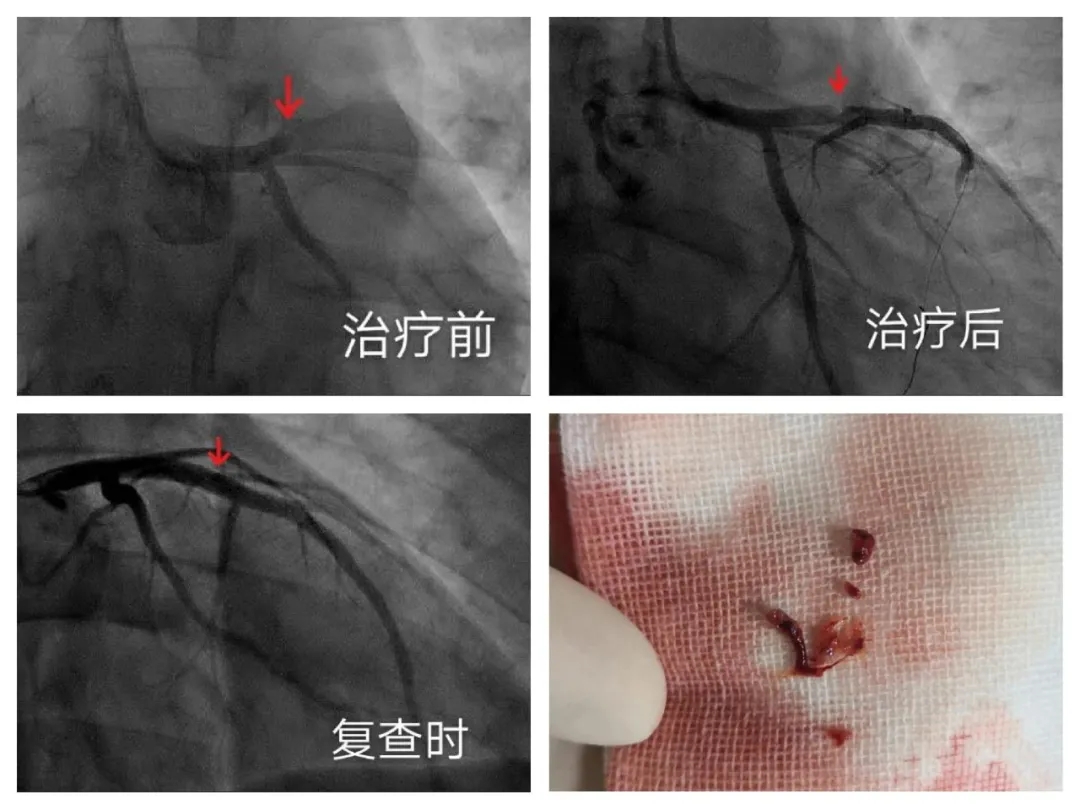

经冠状动脉造影显示,王华的前降支近端发生急性完全闭塞。在心内科主任医师裴汉军的带领下,心内科三病区医护人员团结协作,争分夺秒地为王华进行手术,当他们用抽吸导管抽出堵在血管内的一大块血栓后,闭塞的血管又重新恢复了通畅,剧烈胸痛症状随即缓解,整个手术用时不到20分钟。术后经过强化药物治疗,受损血管的创面也及时得到愈合。两周后,患者再次造影复查,发现受损的血管已经恢复如初,既见不到血栓,也没有任何狭窄,并通过心脏彩超检查确认心功能恢复良好。看到儿子康复出院,孩子的父母喜极而泣。